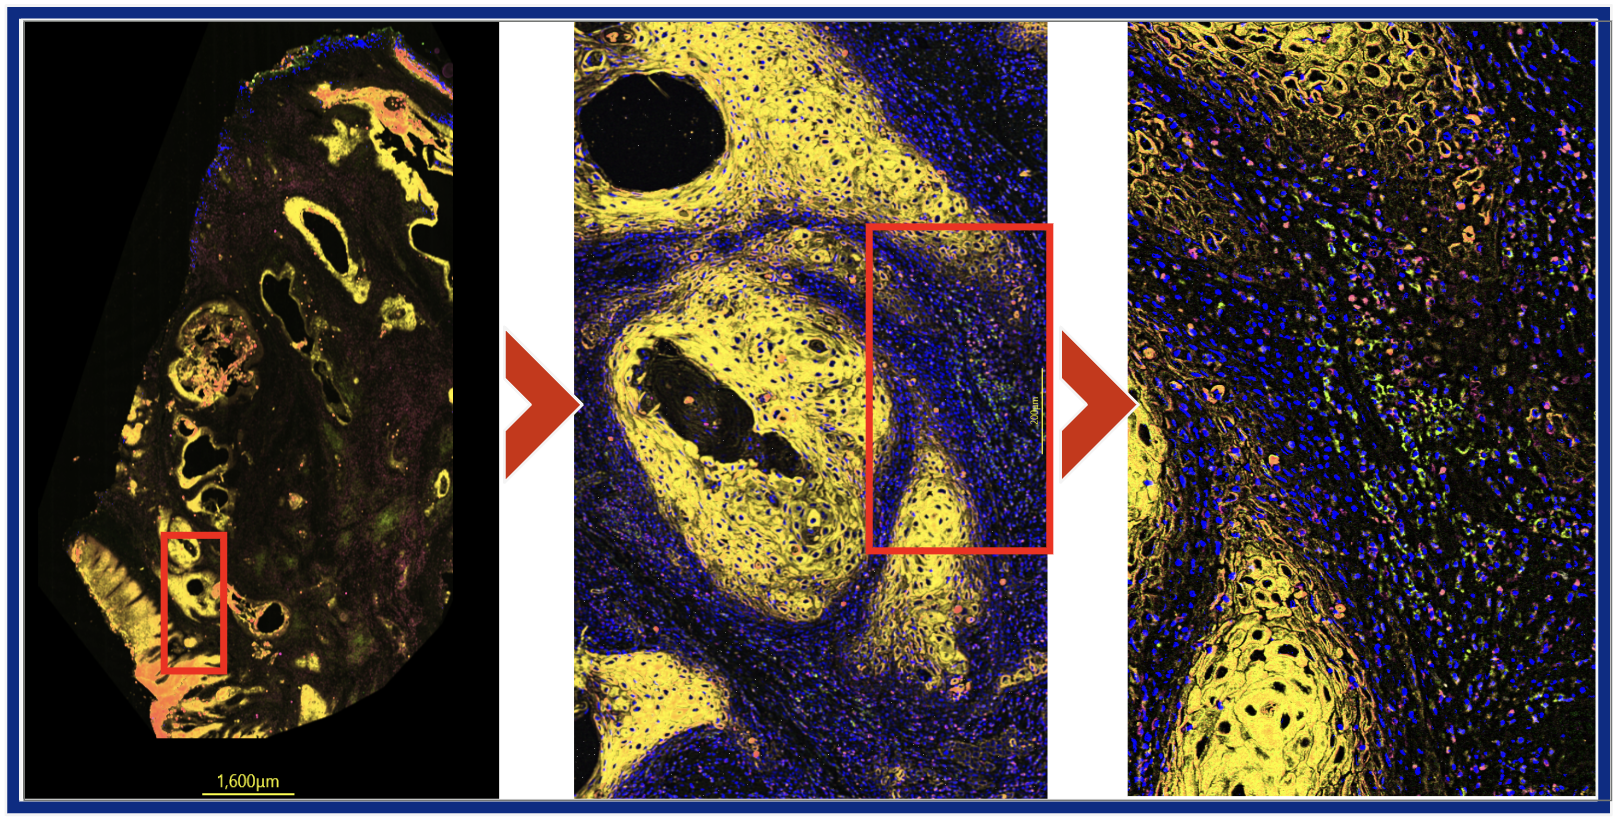

The COLUXA AEON CytoScanner system is a high-throughput laser scanning full spectral fluorescence microscope designed for imaging cells and tissue samples

Subcellular or Whole Tissue

More Information Less Biopsies